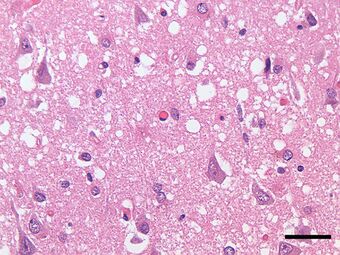

Micrograph showing spongiform degeneration (vacuoles that appear as holes in tissue sections) in the cerebral cortex of a patient who had died of a prion disease (Creutzfeldt-Jakob disease). H&E stain. Scale bar = 30 microns (0.03 mm).

Prions cause neurodegenerative disease by aggregating extracellularly within the central nervous system to form plaques known as amyloids, which disrupt the normal tissue structure. This disruption is characterized by "holes" in the tissue with resultant spongy architecture due to the vacuole formation in the neurons.[68] Other histological changes include astrogliosis and the absence of an inflammatory reaction.[69] While the incubation period for prion diseases is relatively long (5 to 20 years), once symptoms appear the disease progresses rapidly, leading to brain damage and death.[70] Neurodegenerative symptoms can include convulsions, dementia, ataxia (balance and coordination dysfunction), and behavioural or personality changes.[citation needed]